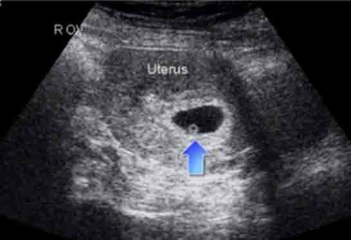

• 4. Hafta: Gebelik testi genellikle bu hafta yapılır. Anne adayı, adet döneminin gecikmesi gibi belirtiler hissedebilir.

• 5. Hafta: Fetüs büyümeye başlar ve kalp atışları duyulmaya başlanabilir. Anne, mide bulantısı ve yorgunluk gibi belirtiler yaşayabilir.